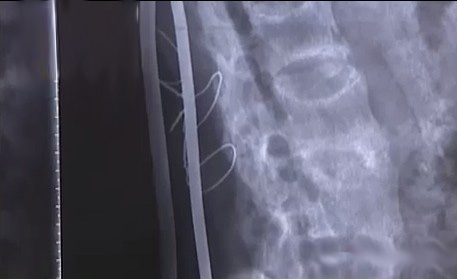

“我从没敢寻思做手术取钢筋的事儿。”病床上的伊振江说,当年腰椎和胸椎被砸伤后,后背就下了两根40厘米长的固定钢筋,“医生建议钢筋在体内最长时间不能超过两年,可我却没有。”

“这17年我从未平躺睡过一觉,只有左右侧卧两个动作。”伊振江说,5年前,一根钢筋竟然从腰部支出了一个小头,一个来月后,钢筋的上下两头都崩出了体内,伤口开始发炎化脓。“我也意识到该把钢筋拿出来,可自己没了这个能力,只能挺。”